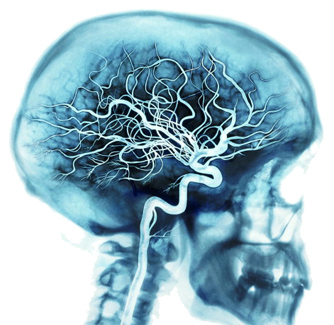

2. Linhas de alimentação

O cérebro é alimentado por uma das redes de vasos sanguíneos mais ricas do corpo.

A cada batimento cardíaco, as artérias transportam de 20 a 25 por cento do seu sangue para o cérebro, onde bilhões de células utilizam cerca de 20 por cento do oxigênio e do combustível que o sangue transporta.

Quando você está pensando muito sobre algo, seu cérebro pode usar até 50 por cento do oxigênio e combustível.

Toda a rede de vasos inclui veias e vasos capilares, além das artérias.